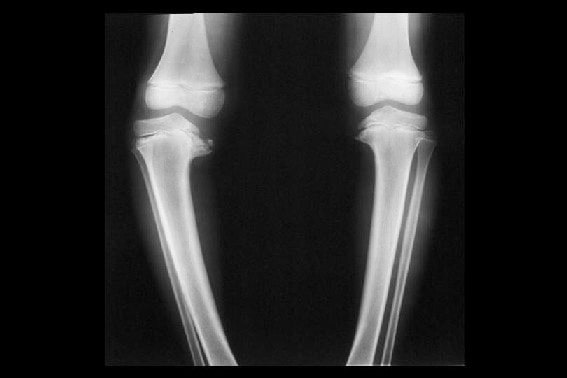

این شرایط کاملاً قابلشناسایی هستند. در صورتی که شما دچار مشکل پا پرانتزی شوید، زانوهای شما در زمان ایستادن در حالتی که پاها و قوزکهای آن در کنار یکدیگر باشند، از هم فاصله میگیرند. زانوی پرانتزی یک مشکل متقارن است که امکان مشاهده آن در هر دو پا وجود دارد.

تشخیص مشکل پا پرانتزی به سادگی امکانپذیر است، اما پزشک میتواند درباره شدت مشکل یا اینکه این موضوع بهخاطر بیماریهای دیگر تشکیل شده، اطلاعات لازم را در اختیار شما قرار دهد. در طول جلسه ملاقات با پزشک، معمولاً معاینات لازم بر روی پای کودک انجام شده و وضعیت راهرفتن وی بررسی میشود. علاوه بر این پزشک ممکن است از عکسبرداری رادیولوژی زانوها و آزمایش خون برای تأیید تشخیص علت مشکل استفاده کند. در واقع عکسبرداری انجام شده از استخوان میتواند به پزشک در ارتباط با آسیبهای وارد شده به استخوانهای پا و زانو کمک کند و آزمایش خون میتواند ابتلای احتمالی فرد به بیماری پوکی استخوان یا پاژه را مشخص نماید.